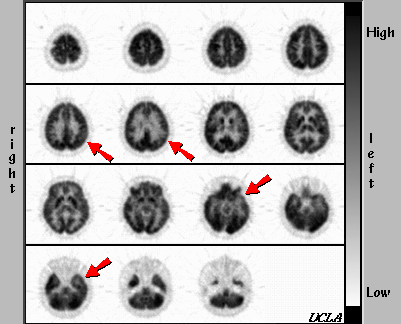

[Return to Case] Correct! Complex Partial Epilepsy of Temporal Lobe Origin The diagnosis of complex partial epilepsy is supported by the relatively decreased cortical metabolism in the left temporal and left parietal sites.

The diagnosis of complex partial epilepsy is supported by the relatively decreased cortical metabolism in the left temporal and left parietal sites.